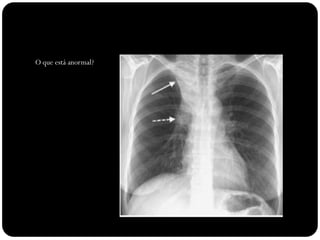

O que está anormal?

Brônquio traqueal

aberrante